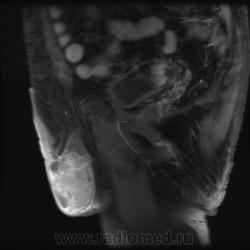

"Мужчина, 60 лет. Около 3 месяцев назад появился дискомфорт в области мошонки, увеличение правого яичка."

Считаю, что семинома - не самый вероятный вариант, т.к. структура опухоли достаточно неоднородная, есть распространение на придаток и границы четкие.

Могу предположить, неоплазию правого яичка.

Я в заключении вынес на первый ряд карциному яичка.